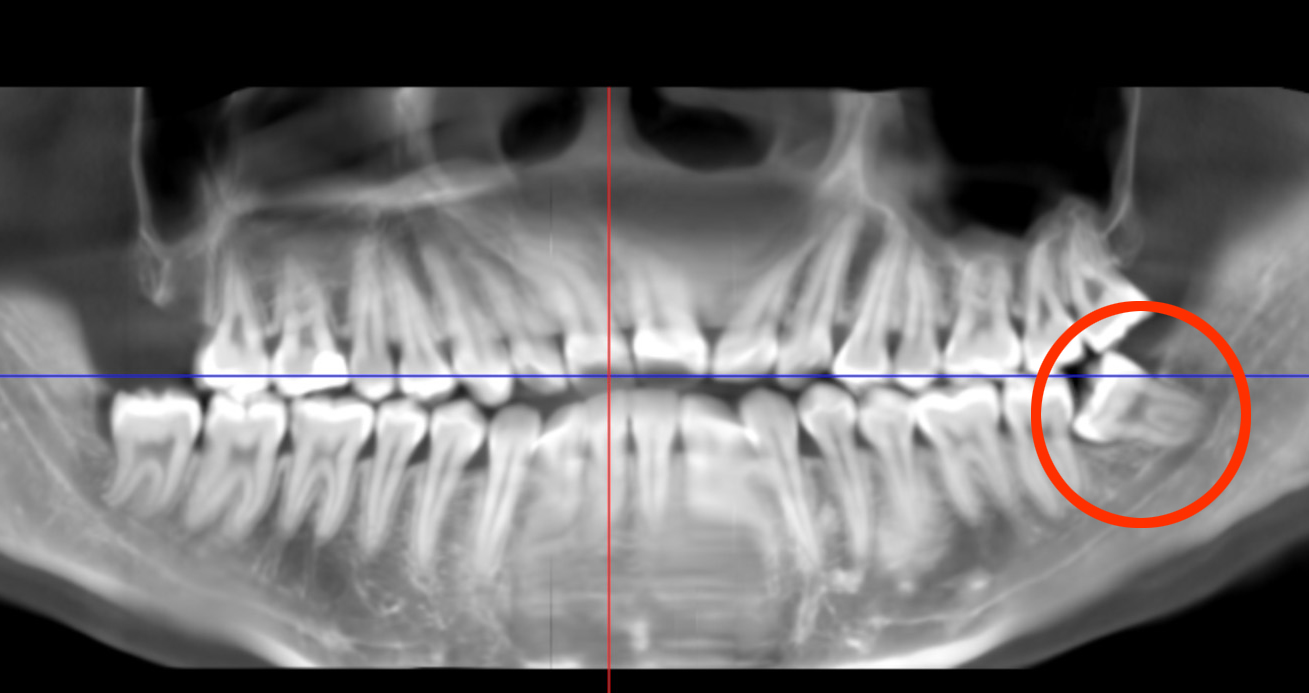

检查显示,崔小姐左侧下颌智齿阻生,紧贴下牙槽神经管

然而,检查结果显示,崔小姐左下智齿深藏于骨组织,牙根部紧贴下牙槽神经管。曾经拔过牙的小伙伴肯定认为她即将留下一段痛苦回忆,并已经开始为她祈祷。